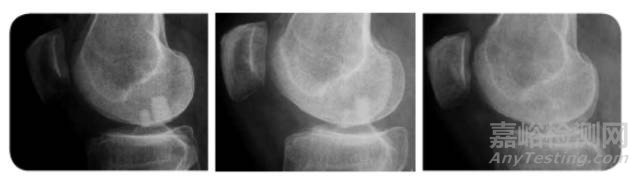

第一例:男,47歲

斯洛維尼亞人,由于打排球時(shí)嚴(yán)重傷了膝蓋軟骨而接受治療。在2011年六月接受手術(shù)后的六個(gè)月后,便能夠參加他所愛的滑雪運(yùn)動(dòng),并且在隔年,完成了180公里的自行車馬拉松。

術(shù)后3周 術(shù)后6周 術(shù)后12周